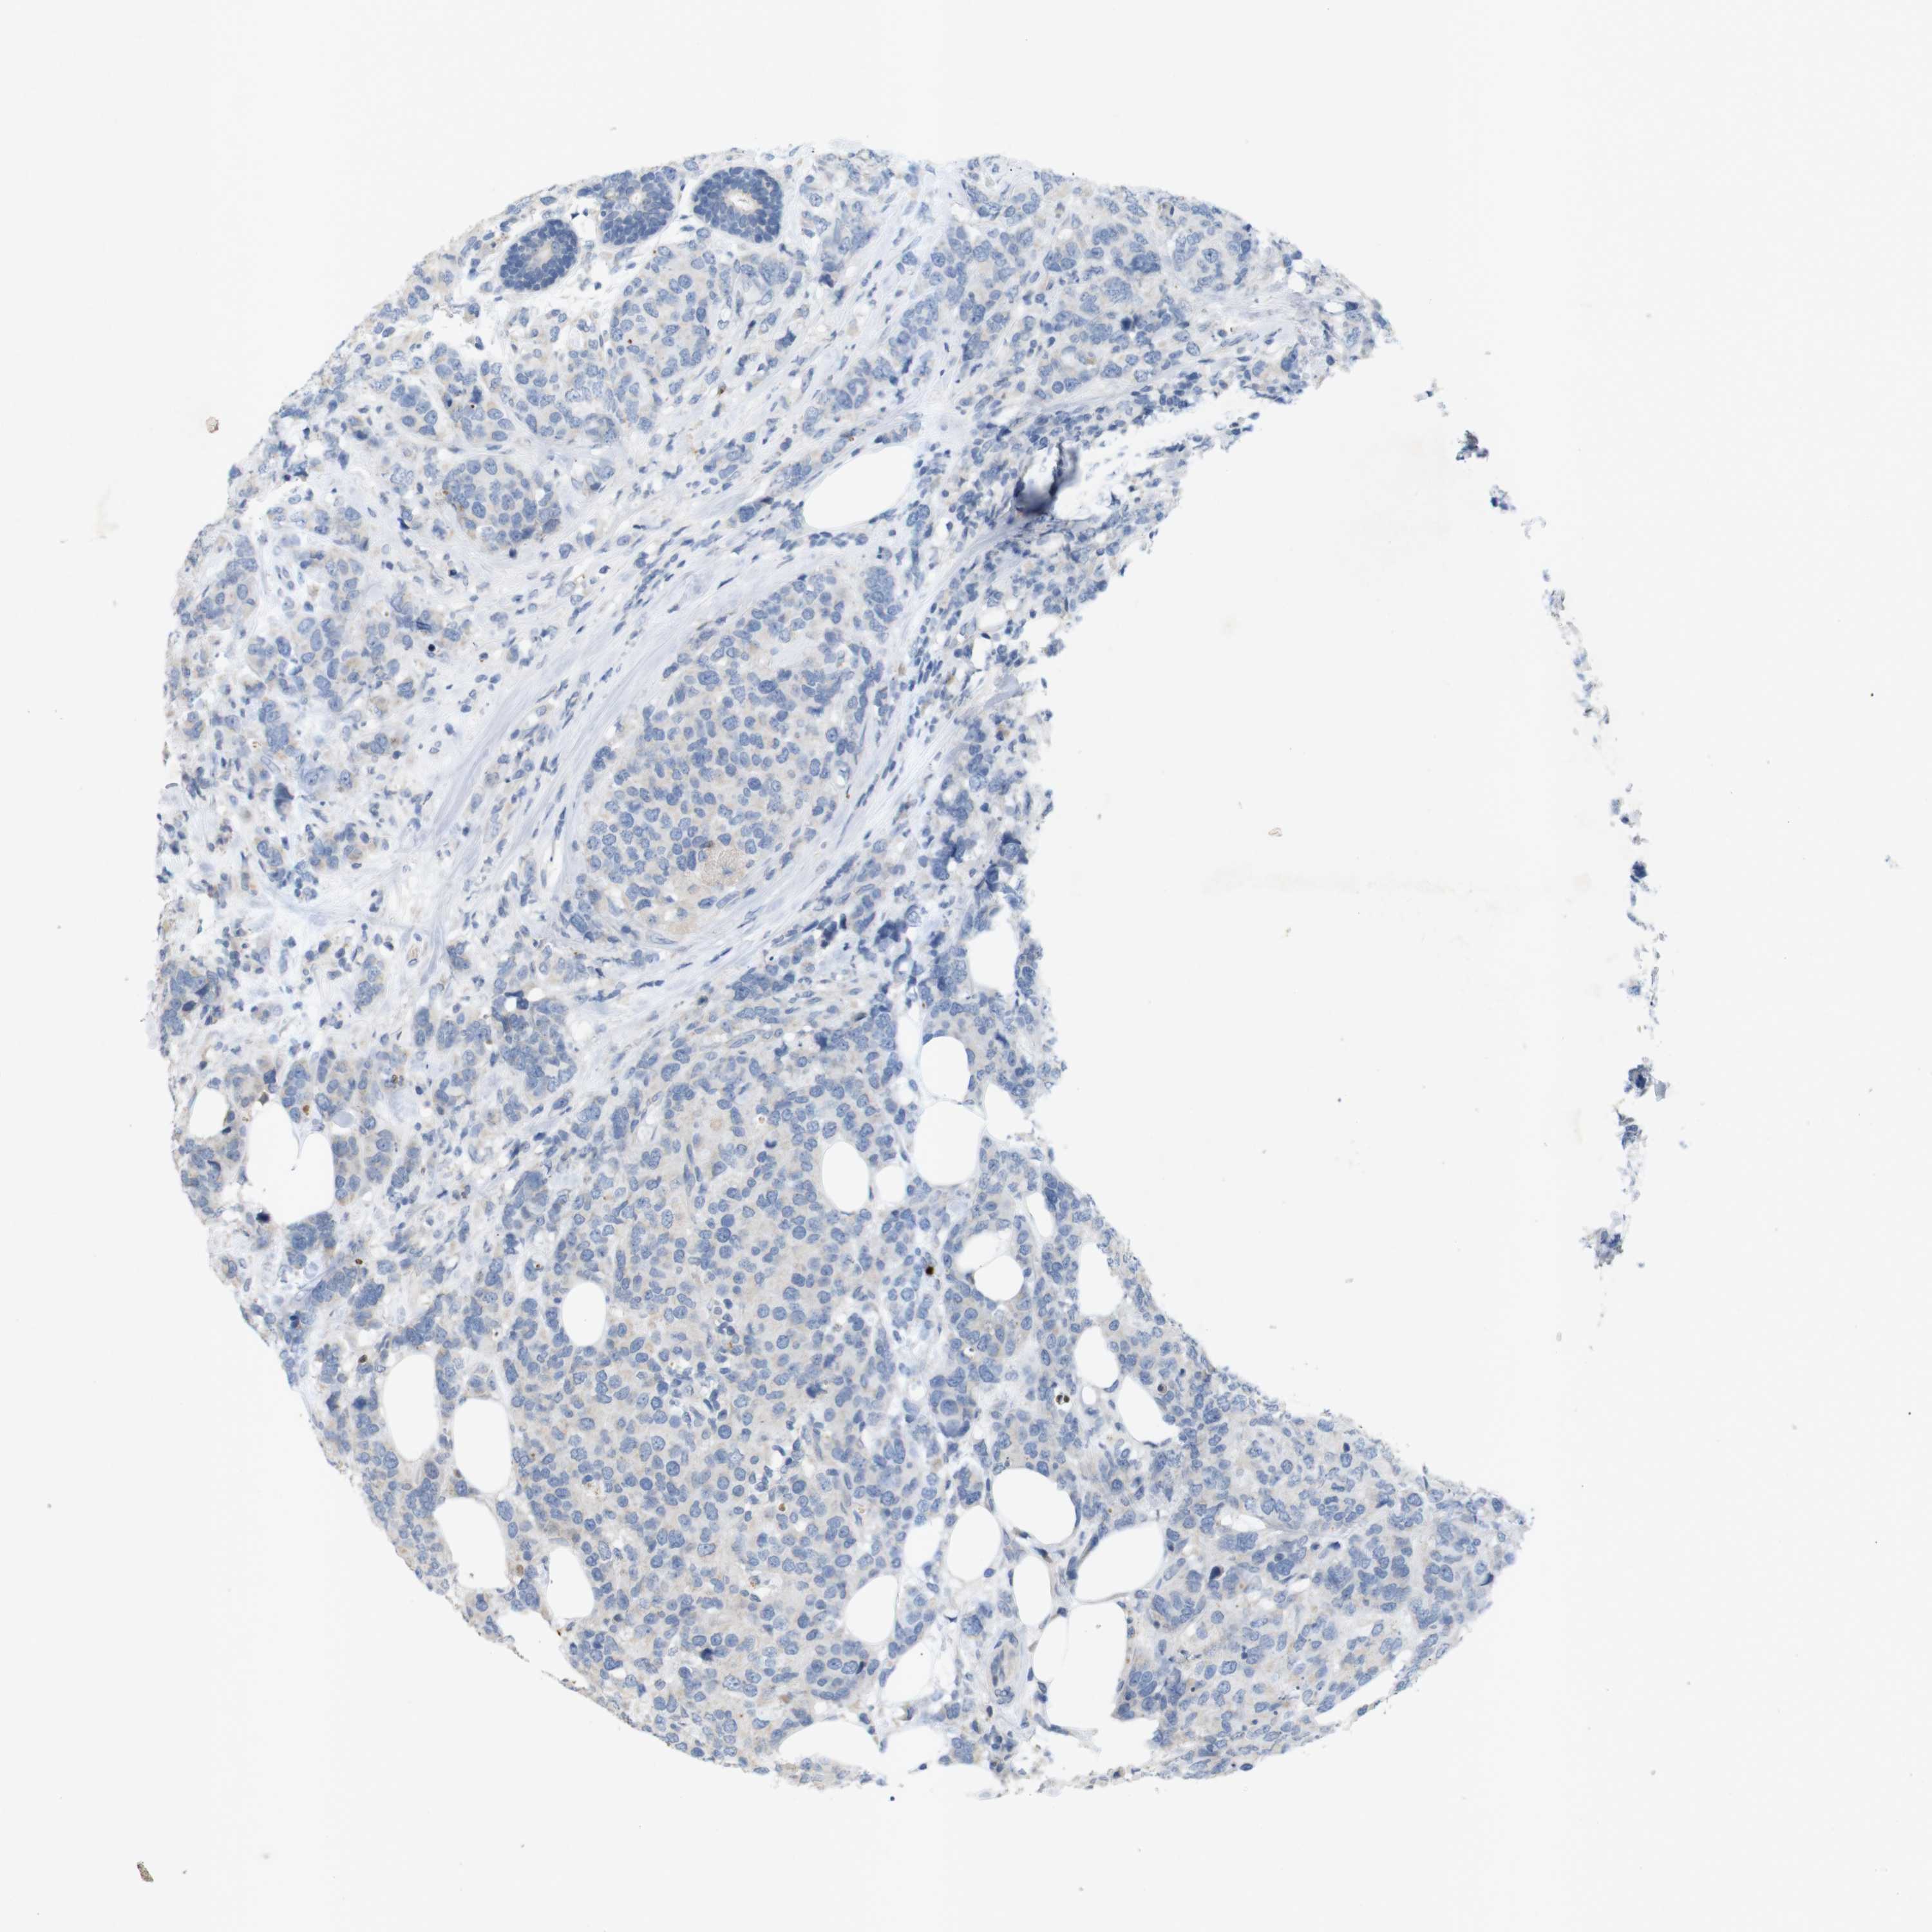

BRCA TCGA BRCA VALIDATION PROTEIN EXPRESSION

ANTIBODIES

AND

VALIDATION